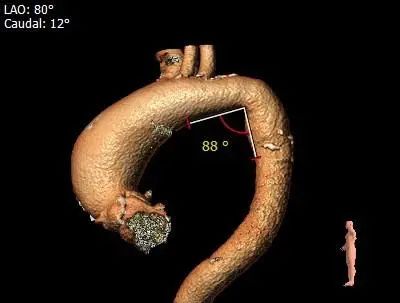

3.接近横位心,升主动脉扭曲,弓顶部角度略锐,宽度适宜,预计输送器可顺利过弓,输送器跨瓣难度增高,必要时Snare辅助。

2.接近横位心,升主动脉严重扩张并扭曲,跨瓣、球囊及输送器跨瓣难度增高

4.接近横位心,升主动脉严重扩张扭曲,输送器及球囊跨瓣难度高,必要时Snare辅助。

5.弓顶部角度略锐,宽度适宜,预计输送器可顺利过弓。